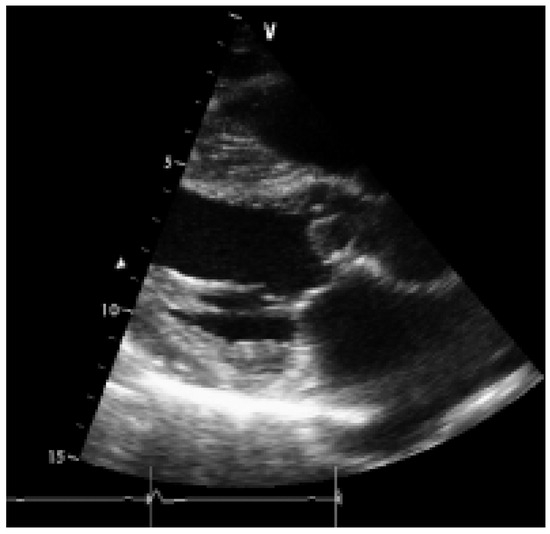

While substantial progress has been made over the past decade in the medical treatment of heart failure, certain patients fail to respond to optimal treatment despite the availability of excellent drugs. Cardiac resynchronisation therapy, or multisit...